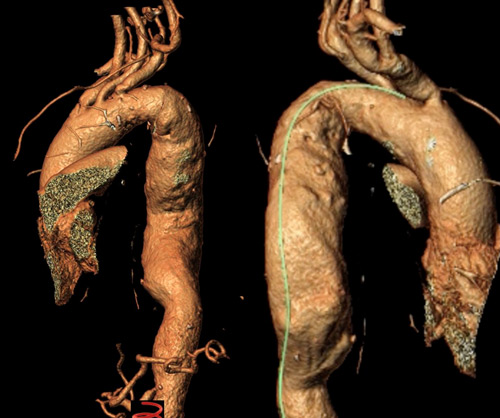

Distal optimisation and future treatment option

- Further extension of the 37 x 200 mm Gore® TAG® Conformable with a large diameter tapered 37/31 x 150 mm TAG® Conformable

- At the same time, preparation for a potential later extension into the abdominal aorta, should the disease progress and become treatment-indicated in this segment.

- Reduction of the risk of a distal stent graft–induced new entry (dSINE) and improved adaptation to the patient’s anatomy.

- Branched and tapered endovascular solutions can optimise both proximal and distal sealing zones.

- Tapered stent-graft configurations may reduce wall-stress–related stent graft–induced new entry (SINE).

- Both concepts enable an endovascular repair strategy tailored to the individual patient’s anatomy and pathology.

- Tapered solutions provide an additional option to facilitate future extensions without the need for further custom-made components.